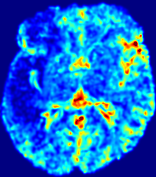

LesionRefer to captionRefer to captionRefer to captionRefer to captionRefer to captionRefer to caption𝐕rgbsubscript𝐕𝑟𝑔𝑏{\bf{V}}_{rgb}Refer to captionRefer to captionRefer to captionRefer to captionRefer to captionRefer to caption𝐕2subscriptnorm𝐕2{\|\bf{V}}\|_{2}Refer to captionRefer to captionRefer to captionRefer to captionRefer to captionRefer to captionRefer to caption3.53.53.52.82.82.82.12.12.11.41.41.40.70.70.70.00.00.0(mm/s)𝑚𝑚𝑠(mm/s)D𝐷DRefer to captionRefer to captionRefer to captionRefer to captionRefer to captionRefer to captionRefer to caption0.0200.0200.0200.0160.0160.0160.0120.0120.0120.0080.0080.0080.0040.0040.0040.0000.0000.000(mm2/s)𝑚superscript𝑚2𝑠(mm^{2}/s)Slice #1Slice #2Slice #3Slice #4Slice #5Slice #6

Figure 4: PIANO feature maps for another patient in the ISLES 2017 training set, where the lesion is located in the right hemisphere. Top row: segmented stroke lesion region (white) on different slices. The corresponding slices for the PIANO feature maps are shown in the following rows.

For a better insight into an estimated velocity field 𝐕𝐕{\bf{V}} and diffusion field 𝐃𝐃{\bf{D}}, we compute the following maps: (1) 𝐕rgbsubscript𝐕𝑟𝑔𝑏{\bf{V}}_{rgb}: Color-coded orientation map of 𝐕=(Vx,Vy,Vz)T𝐕superscriptsuperscript𝑉𝑥superscript𝑉𝑦superscript𝑉𝑧𝑇{\bf{V}}=(V^{x},V^{y},V^{z})^{T}, obtained by normalizing 𝐕𝐕{\bf{V}} to unit length and mapping its 3 components to red, green, blue respectively; (2) 𝐕2subscriptnorm𝐕2\|{\bf{V}}\|_{2}: 222 norm of 𝐕𝐕{\bf{V}}; (3) D𝐷D: scalar field in Eq. 5.

Fig. 3 and Fig. 4 show the PIANO feature maps estimated from two ISLES 2017 patients: all are highly consistent with the lesion in both cases. Details of the blood flow trajectories are revealed in 𝐕rgbsubscript𝐕𝑟𝑔𝑏{\bf{V}}_{rgb} by the ridged patterns and the sharp changes of colors in the unaffected (right) hemisphere, while the flat patterns appearing within the lesion provide little directional information about the velocity and indicate low velocity magnitudes. Velocity magnitudes are more directly visualized via 𝐕2subscriptnorm𝐕2\|{\bf{V}}\|_{2}, from which one can easily locate the lesion where 𝐕2subscriptnorm𝐕2\|{\bf{V}}\|_{2} is low. D𝐷D also indicates lower diffusion values in the lesion, though with less contrast potentially due to the fact that it captures the accumulated effect of CA diffusion at the voxel-level.